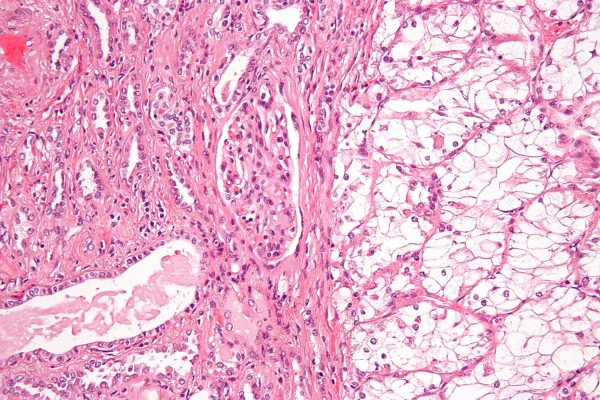

Καρκίνωμα νεφρικών κυττάρων

Ο Gabriele Sorce, M.D., από το Επιστημονικό Ινστιτούτο IRCCS San Raffaele στο Μιλάνο, Ιταλία, και οι συνεργάτες του συνέκριναν τη θνησιμότητα λόγω καρκίνου μεταξύ ασθενών με κλινικό καρκίνωμα νεφρικών κυττάρων σταδίου T1a που έλαβαν θεραπεία με κρυοκατάλυση ή θερμική κατάλυση. Τα δεδομένα συμπεριλήφθηκαν για 1.080 και 388 ασθενείς με μέγεθος όγκου 3,1 έως 4 cm. μετά από αντιστοίχιση βαθμολογίας τάσης έως και 2:1, συμπεριλήφθηκαν 757 κρυοεκτομές και 388 θερμικές εκτομές με βάση τη θερμότητα. Επιπλέον, συμπεριλήφθηκαν 3.354 και 1.114 ασθενείς με μέγεθος όγκου ≤3 cm που υποβλήθηκαν σε θεραπεία με κρυοκατάλυση και θερμική αφαίρεση με βάση τη θερμότητα, αντίστοιχα. μετά από αντιστοίχιση βαθμολογίας τάσης έως και 2:1, συμπεριλήφθηκαν 2.217 και 1.114, αντίστοιχα.

Οι ερευνητές διαπίστωσαν ότι η θερμική αφαίρεση με βάση τη θερμότητα συσχετίστηκε με αυξημένη θνησιμότητα λόγω καρκίνου σε σύγκριση με την κρυοεκτομή, μετά από αντιστοίχιση βαθμολογίας τάσης και σε μοντέλα παλινδρόμησης πολυμεταβλητών ανταγωνιστικών κινδύνων για ασθενείς με μέγεθος όγκου 3,1 έως 4 cm (αναλογία κινδύνου, 2,02, 95 τοις εκατό εμπιστοσύνη διάστημα, 1,29 έως 3,17, P < 0,001). Μεταξύ ασθενών με μέγεθος όγκου ≤3 cm, η θερμική κατάλυση με βάση τη θερμότητα δεν συσχετίστηκε με αυξημένη θνησιμότητα λόγω καρκίνου σε σύγκριση με την κρυοκατάλυση (αναλογία κινδύνου, 1,13, 95 τοις εκατό διάστημα εμπιστοσύνης, 0,80 έως 1,58, P = 0,5).